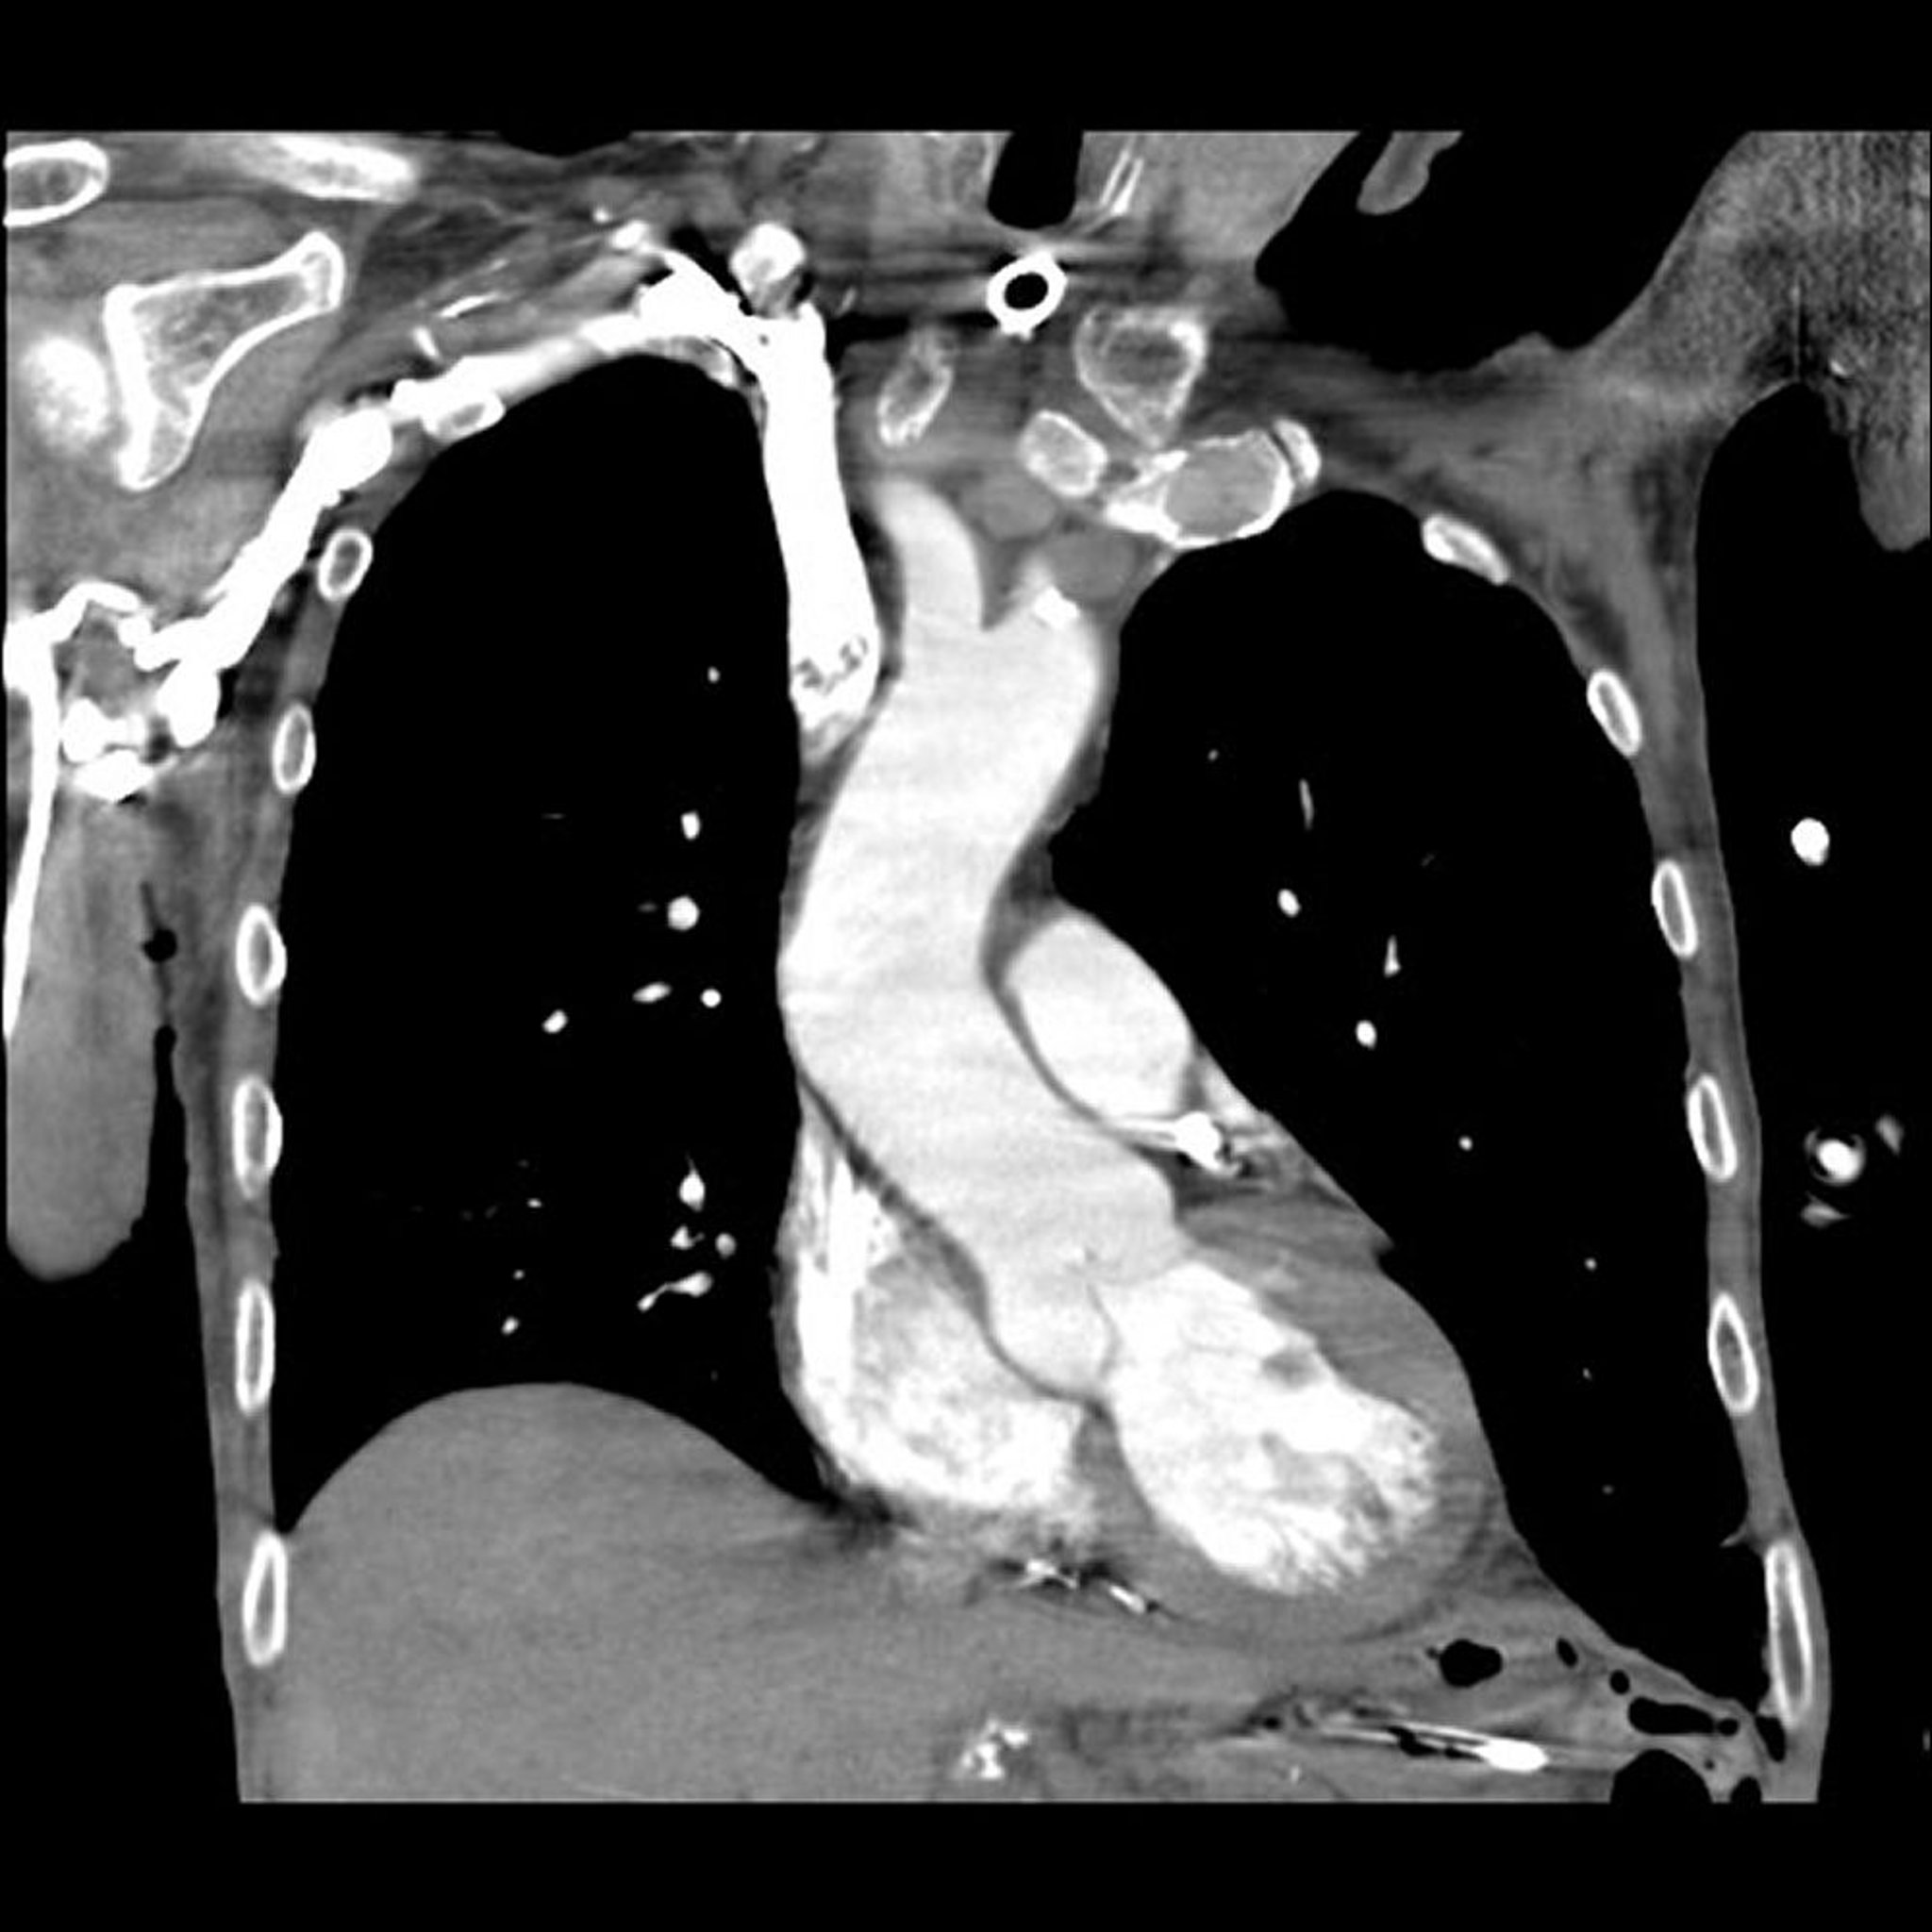

CT एंजियोग्राफ़ी

CT एंजियोग्राफ़ी में CT और एक रेडियोपैक कंट्रास्ट एजेंट का इस्तेमाल करके रक्त वाहिकाओं की 2- और 3-डायमेंशनल इमेज बनाई जाती हैं, जिनमें वो धमनियां भी शामिल हैं (कोरोनरी धमनियां) जो हृदय में रक्त की आपूर्ति करती हैं। कंट्रास्ट एजेंट को आमतौर पर बांह में एक नस (बरसों से की जाने वाली एंजियोग्राफ़ी की तरह धमनी में नहीं) में इंजेक्ट किया जाता है। इन इमेज को तेज़ी से लिया जाता है और इमेज पर समय भी डाला जाता है ताकि मूल्यांकन की जा रही रक्त वाहिकाओं से होकर बहने वाले रेडियोपैक कंट्रास्ट एजेंट को इन इमेज में दिखाया जा सके। कंप्यूटर इन इमेज से सभी ऊतकों को डिजिटल रूप से हटा देता है, रक्त वाहिकाओं को छोड़कर। (कोरोनरी एंजियोग्राफ़ी भी देखें।)

CT एंजियोग्राफ़ी का उपयोग इनका पता लगाने के लिए किया जाता है:

• धमनियों में सिकुड़न या रुकावट (जैसे रक्त के थक्के)

• बड़ी धमनियों में उभार (एन्यूरिज्म) और उनका फटना (डिसेक्शन)

• रक्त को ट्यूमर तक ले जाने वाली रक्त वाहिकाओं में असामान्यताएं

पारंपरिक एंजियोग्राफ़ी के बजाय आमतौर पर CT एंजियोग्राफ़ी का उपयोग किया जाता है क्योंकि यह सुरक्षित और कम आक्रामक है (इसमें धमनी में कैथेटर डालने की आवश्यकता नहीं होती है, जिसमें नस में कैथेटर डालने की तुलना में थोड़ा अधिक जोखिम होता है)। CT एंजियोग्राफ़ी रक्त वाहिकाओं की असामान्यताओं को मैग्नेटिक रीसोनेंस एंजियोग्राफ़ी जितना ही सटीक रूप से दिखाती है, लेकिन यह पहले से की जाने वाली एंजियोग्राफ़ी तकनीक की तुलना में थोड़ा कम सटीक है।

CT एंजियोग्राफ़ी में आमतौर पर केवल 1 से 2 मिनट का समय लगता है।